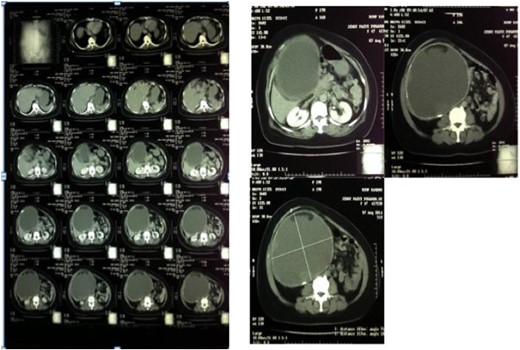

The abdominal wall appeared asymmetrical due to the right upper abdominal mass. Abdominal palpation found a mass with a size of 27 × 25 × 12 cm, a mobile, cystic, smooth surface and no tenderness. This cystic mass extends from the right hypochondriac to the right illiac region of the abdomen. Laboratory test results were unremarkable except for mild leukocytosis (13 500/mm [3]). Ultrasound and computed tomography (CT)-scan showed a cystic mass suggesting a very large gallbladder, expanding from the right hypochondriac to the right illiac fossae of the peritoneal cavity, surrounded by a homogenous capsule (see Fig. 1). The differential impression of this imaging was a mesenterial cyst. After that, the patient was scheduled for elective surgery.

Abdominal CT-scan showed homogenous cystic mass surrounded with a regular wall (left). A cystic mass below the liver expanded to the right lower quadrant of the abdomen (right).